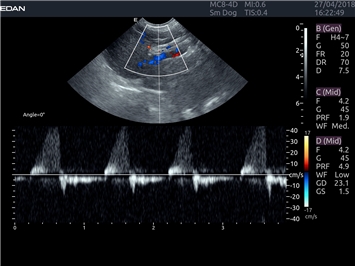

УЗИ-аппарат

EDAN Acclarix LX4 VET

EDAN Acclarix LX4 VET представляет собой профессиональную ультразвуковую систему, специально разработанную для ветеринарных исследований. Сочетание стабильности, высокой производительности и эффективности делает эту систему идеальным выбором для современной ветеринарной практики.

Цветовой допплер:

Да

Импульсно-волновой допплер: